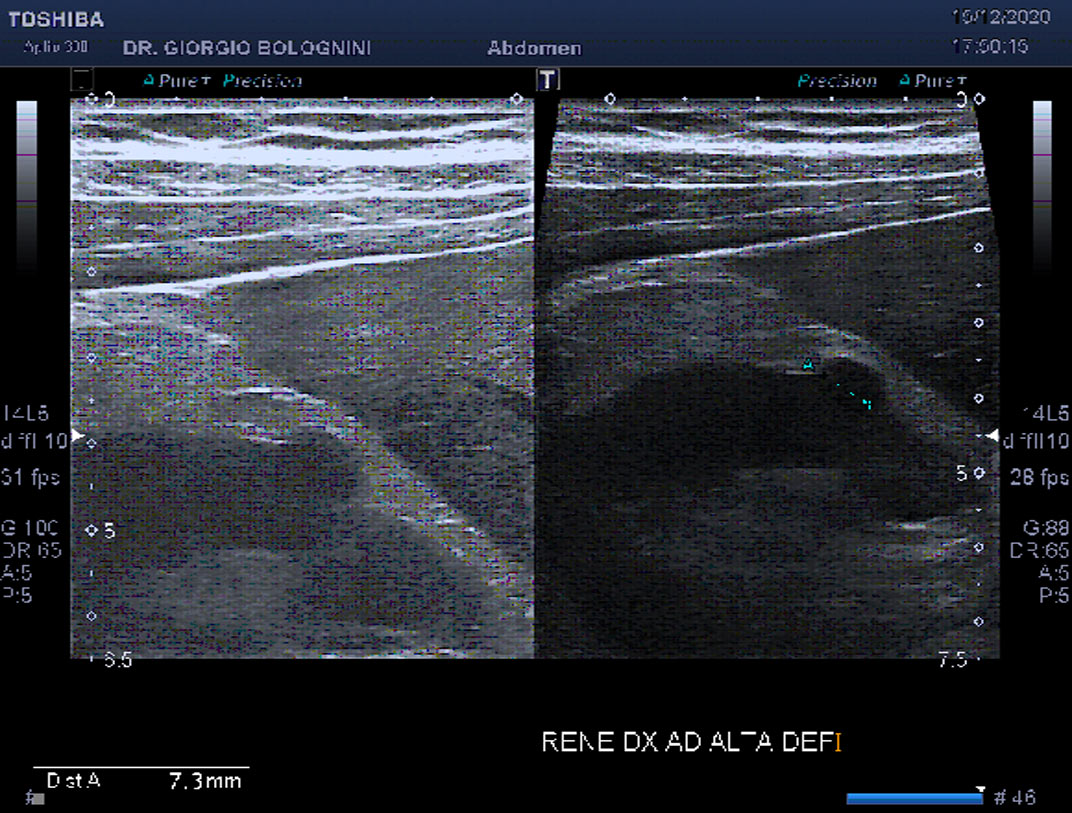

CASO 2 - cisti complessa con deboli segnali vascolari interni, a tipo Bosniak III.

sistema venoso linfatico degli arti inferiori